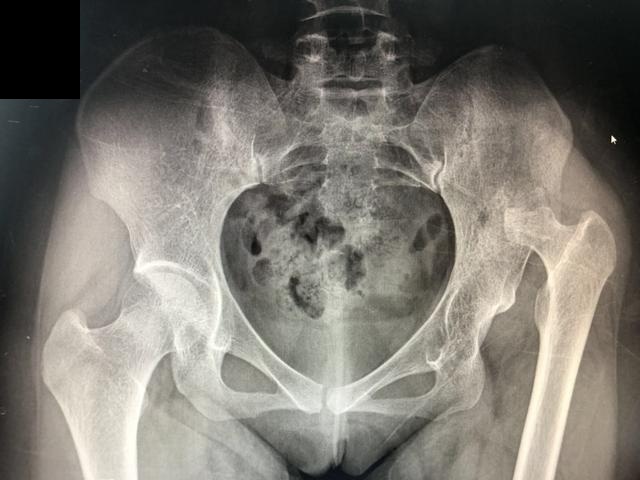

手术后的检查结果如下:

手术后的骨盆正位片

小李手术后1天,便出院回家休养了!